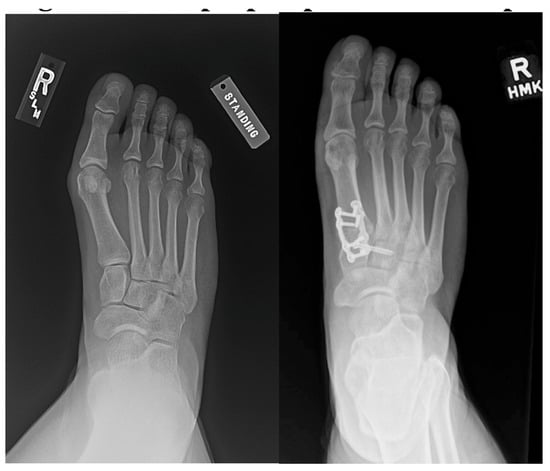

Outcomes of Lapidus Procedure Without Focused Frontal Plane Rotation of the First Metatarsal

J. Am. Podiatr. Med. Assoc. 2026, 116(3), 22; https://doi.org/10.3390/japma116030022 - 23 Apr 2026

Background: We present a retrospective radiographic analysis showcasing the ability to correct hallux valgus using the Lapidus arthrodesis without focused frontal plane rotation of the first metatarsal. Methods: A total of 33 feet in 30 patients who had undergone Lapidus arthrodesis

Background: We present a retrospective radiographic analysis showcasing the ability to correct hallux valgus using the Lapidus arthrodesis without focused frontal plane rotation of the first metatarsal. Methods: A total of 33 feet in 30 patients who had undergone Lapidus arthrodesis for the treatment of hallux abducto valgus deformity from 1 August 2015 to 31 December 2020 were identified. The median age of the cohort was 55.4 years (range, 33–78 years), 23 were female (76.7%), three (10%) underwent bilateral Lapidus arthrodesis, and the median duration of follow-up was 15.9 months (range, 5–72 months). Results: The median (minimum, maximum) preoperative first intermetatarsal angle was 16° (13°, 28°), and at final follow-up it was 5° (0°, 6°) (p < 0.001). The median (minimum, maximum) preoperative hallux abductus angle was 37° (26°, 51°), and at final follow-up it was 8.5° (0°, 22.5°) (p < 0.001). The median (minimum, maximum) preoperative tibial sesamoid position was 6 (4, 7), and at final follow-up it was 3 (2, 5) (p = 0.001). Conclusions: We found the radiographic first metatarsal lateral round sign to be ambiguous. Qualitative comparison of the results of this investigation with prior studies describing outcomes following Lapidus arthrodesis with focused frontal plane rotation of the first metatarsal suggests that similar outcomes can be achieved without employment of a decisive frontal plane rotation of the first metatarsal. Our findings lead us to believe that correction of substantial hallux abducto valgus deformities can be accomplished using the Lapidus procedure combined with lateral release of the first metatarsophalangeal joint without focused derotation of the first metatarsal.